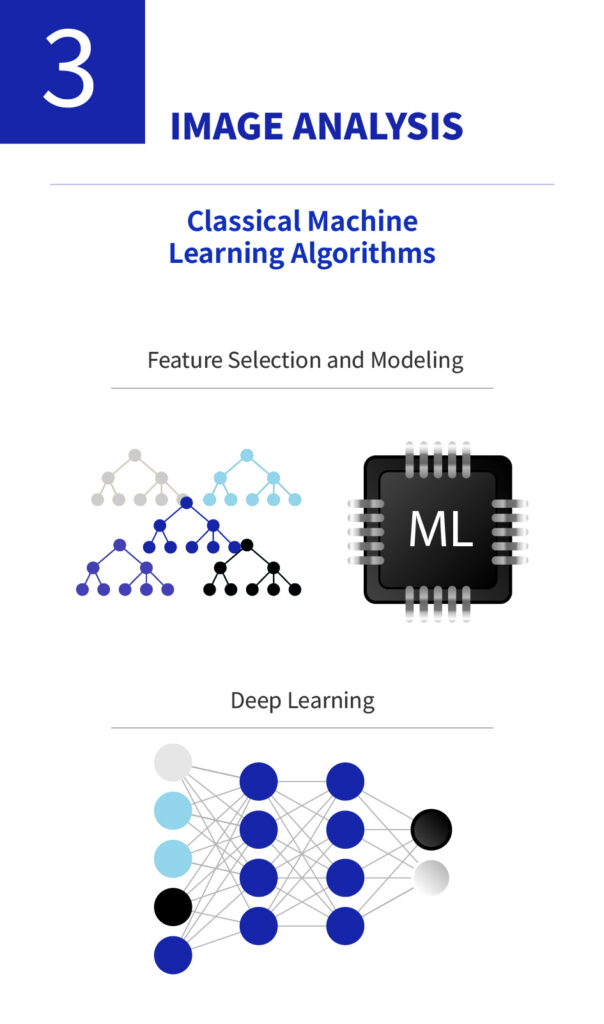

Improving Diagnostic Efficiency and Identifying Disease Associations through AI Technologies

We are enhancing diagnostic accuracy and efficiency by applying AI-based analysis to high-resolution ocular imaging data. By training machine learning models on micro-level features such as leukocyte movement, goblet cell density, and vascular patterns, we aim to uncover associations with various ocular diseases and broader systemic inflammatory or autoimmune conditions.

To support this, we are increasing investments in software and AI infrastructure, with plans to extend our AI diagnostic applications to areas such as systemic disease evaluation and drug response prediction in the near future.

Artificial Intelligence